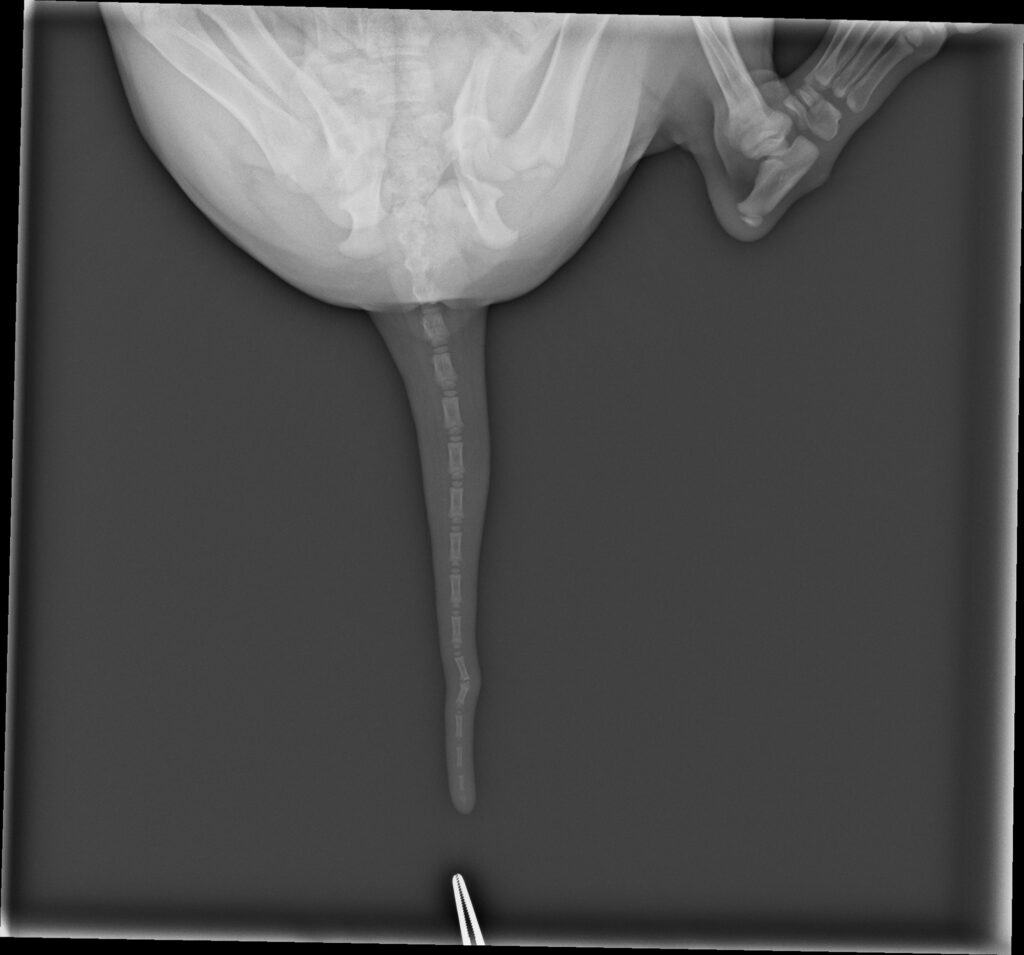

Eigentlich hatten wir vor eine Hündin für die Zucht zu behalten, aber es sollte nicht sein. Blueberry hat leider eine Knickrute und ist somit aus der Zucht ausgeschlossen. Nun beginnt die Suche in Deutschland nach einem passenden Familienmitglied!